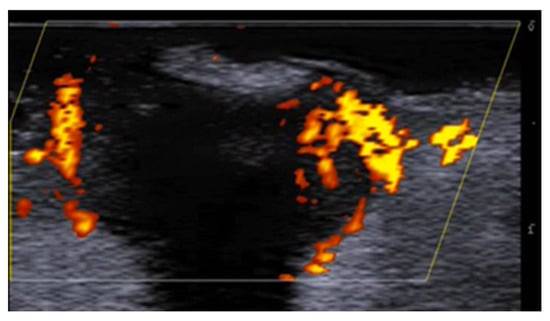

5. Specific Cutaneous Structure and Sites of Skin Disorders

6. Vascular Disorders

8. Neoplastic Diseases

9. Aesthetic Medicine